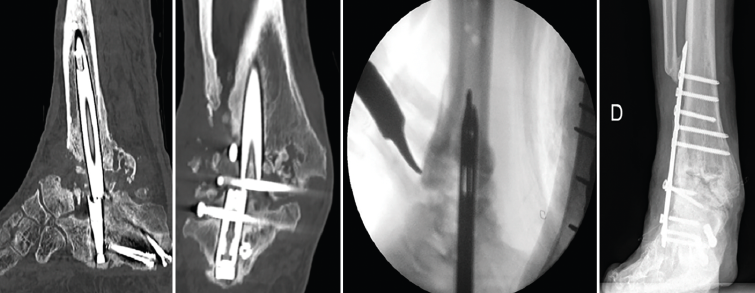

Se reintervino al paciente realizando la extracción del fragmento distal del clavo con el sistema extractor del mismo. Para la extracción del extremo proximal fue necesario, además de la utilización de las guías curvadas, abordar el foco de la pseudoartrosis hasta visualizar el clavo y, con una fresa de alta velocidad, hacer una muesca en el mismo. Mediante la percusión sobre un escoplo apoyado en la muesca realizada en el clavo y con la ayuda de las agujas guía introducidas a través del clavo, se consiguió la extracción del extremo proximal a través de la planta del pie (Figura 3). Se legró la superficie articular tibiotalar y se colocó injerto de cresta ilíaca, fijando la artrodesis con una placa TTC (Palex Medical), aunque la articulación subtalar estuviese artrodesada, para dar mayor solidez al montaje.

Figura 3. Imágenes del clavo tibiotalocalcáneo roto a través de la trinchera ósea y maniobra de extracción con guías endomedulares ayudadas por la impactación directa en la muesca realizada en el clavo.